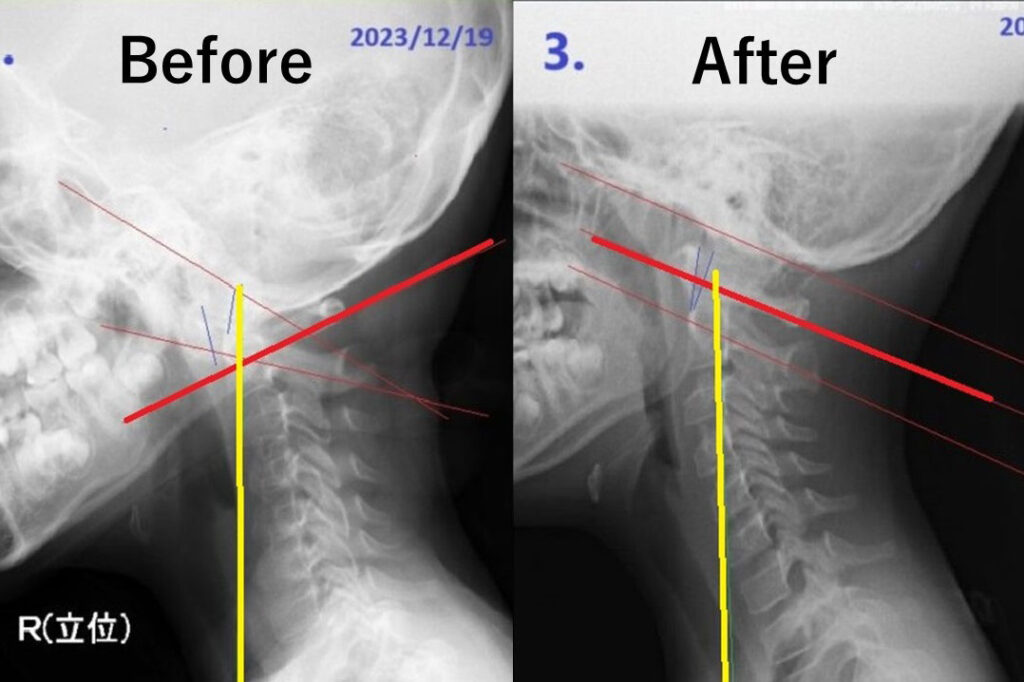

- 当院のアトラスオーソゴナルカイロプラクティックは、より正確なアジャストメントを目指し、水平な第一頚椎(アトラス)に対し垂直な頭と首の関係性にこだわり、脊柱全体をダイナミックに最適化します。

「アトラスを基準とした構造の適正化」で、的確な改善を約束

症状を追って局所的に矯正するのではなく、「第一頚椎(アトラス)に特化したアプローチ」で、頚椎・背骨・腰椎の骨組み全体を構造的に変化させ神経症状を取り除きます。

当院の施術は、人体の重心を適正化させバランスをダイナミックに変化させることで、骨格系や神経系に的確な改善を促します。